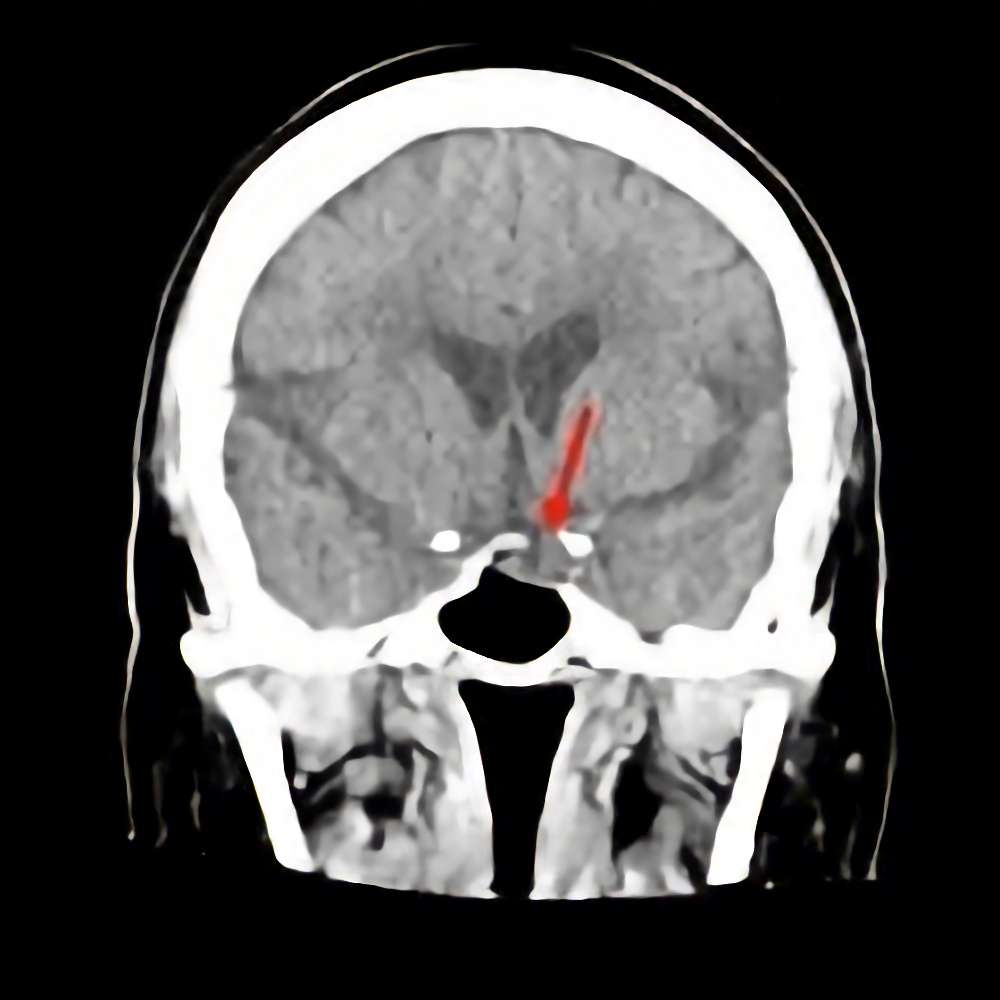

症例 '16年7月

No.

※ 画像をクリックすると拡大表示します。症例No.は平成29年から起算しています。

年_番号

手術年月

患者年齢

’16_111

'16年7月

70代

病名

術式

備考

下垂体腫瘍

断層撮影

手術前

1

手術前2

手術後